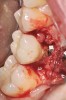

Fig 1. Chipping of veneering porcelain of porcelain-fused-to-gold full-arch fixed dental

prosthesis.

Fracture/Chipping of the Veneering Material

With 5-year complication rates from 3.2% to 25.5%,1 chipping of the veneering material (Figure 1) is the most common technical complication addressed in the literature.1,2 This can be minimized by designing the prosthesis before the final fabrication to ensure optimal framework design and thickness of the veneering material. Following basic occlusal principles in implant prosthodontics is essential. These include reduced cuspal inclination, narrow occlusal table, correction of load direction, reduced nonaxial loading, reduced length of the cantilever, and lighter occlusal contacts on implants.5 Restorations such as monolithic zirconia (Figure 2) and lithium disilicate are also being used to minimize chipping. However, long-term follow-up information on these restorations is limited.